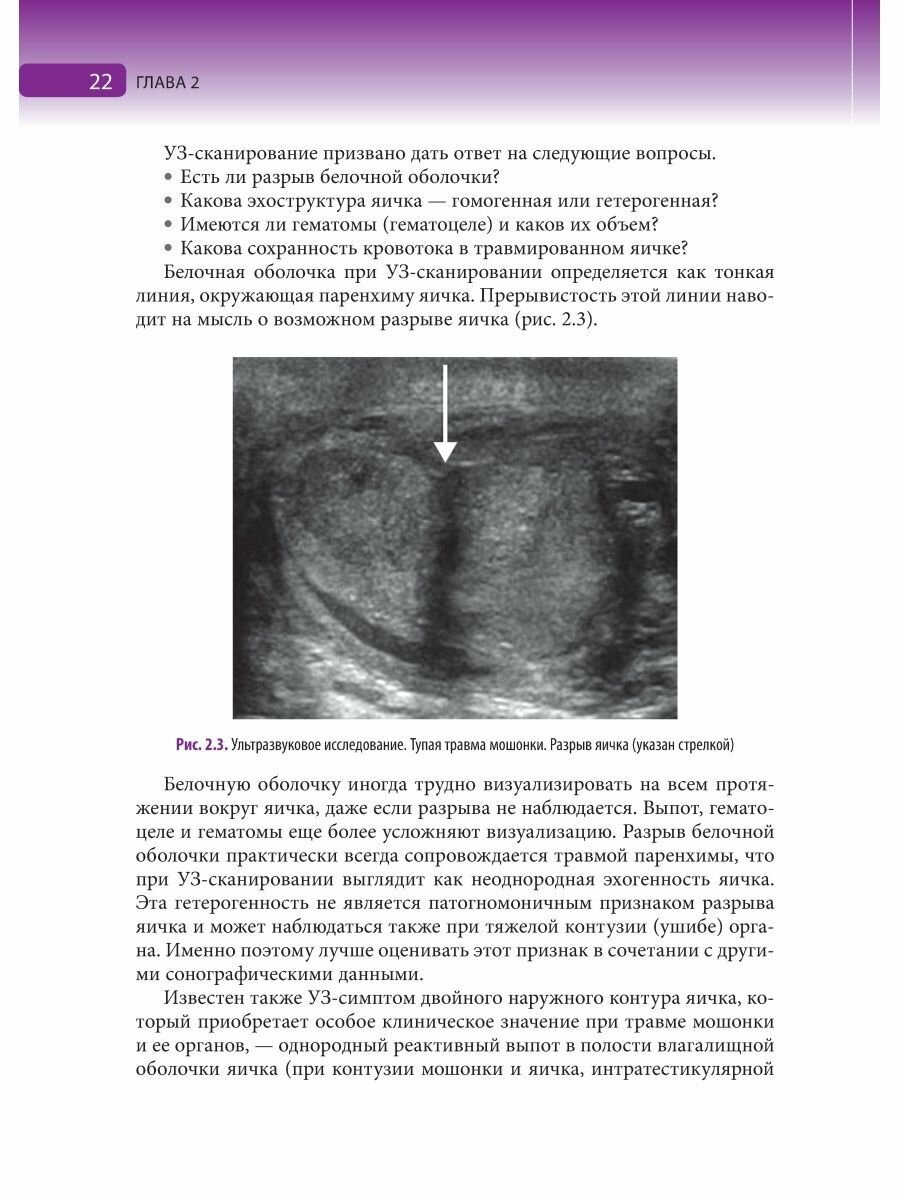

Травмы органов мошонки. Иллюстрированное руководство (Яровой Сергей Константинович, Касатонова Елена Владимировна, Хромов Роман Александрович); ГЭОТАР-Медиа, ГЭОТАР-Медиа, 2020